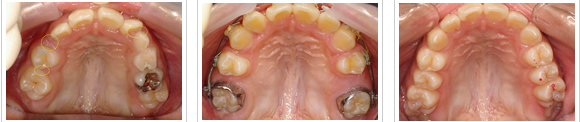

| 40代の女性 左下に3本の歯が虫歯で喪失。 取り外しの入れ歯は入れたくない。 黄色の部位に3本のインプラントを埋入。 |

7年後 違和感もなく、良く噛めていると 満足されています。 |